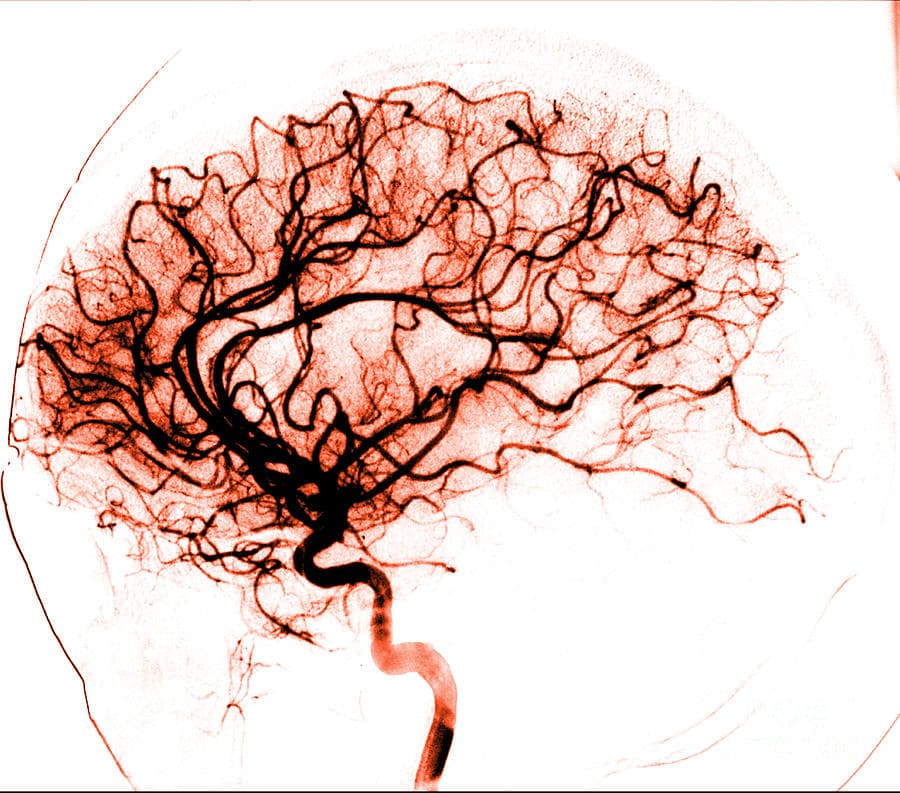

الأوعية الدموية المغذية

الصورة الشريانية الدماغية